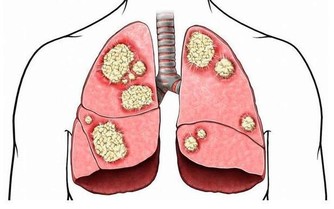

據美國紐約一家專門從事癌症研究的權威機構透露,

中國和日本婦女乳腺癌的發病率比西方低得多,這是為什麼呢?

科學家在比較了世界各國的三餐食譜後得出結論:是由於中國和日本婦女多吃大白菜的緣故。

調查資料表明,每10萬名婦女中,每年乳腺癌的發病率為:中國9人,日本21人,北歐84人,美國91人。

大白菜何來如此神功?

實驗證明,大白菜所含有的許多物質具有防癌抗癌的作用,

因此在美國國立癌症研究所發表的防癌食品排行榜中將白菜排在僅次於大蒜的後面,名列第二。